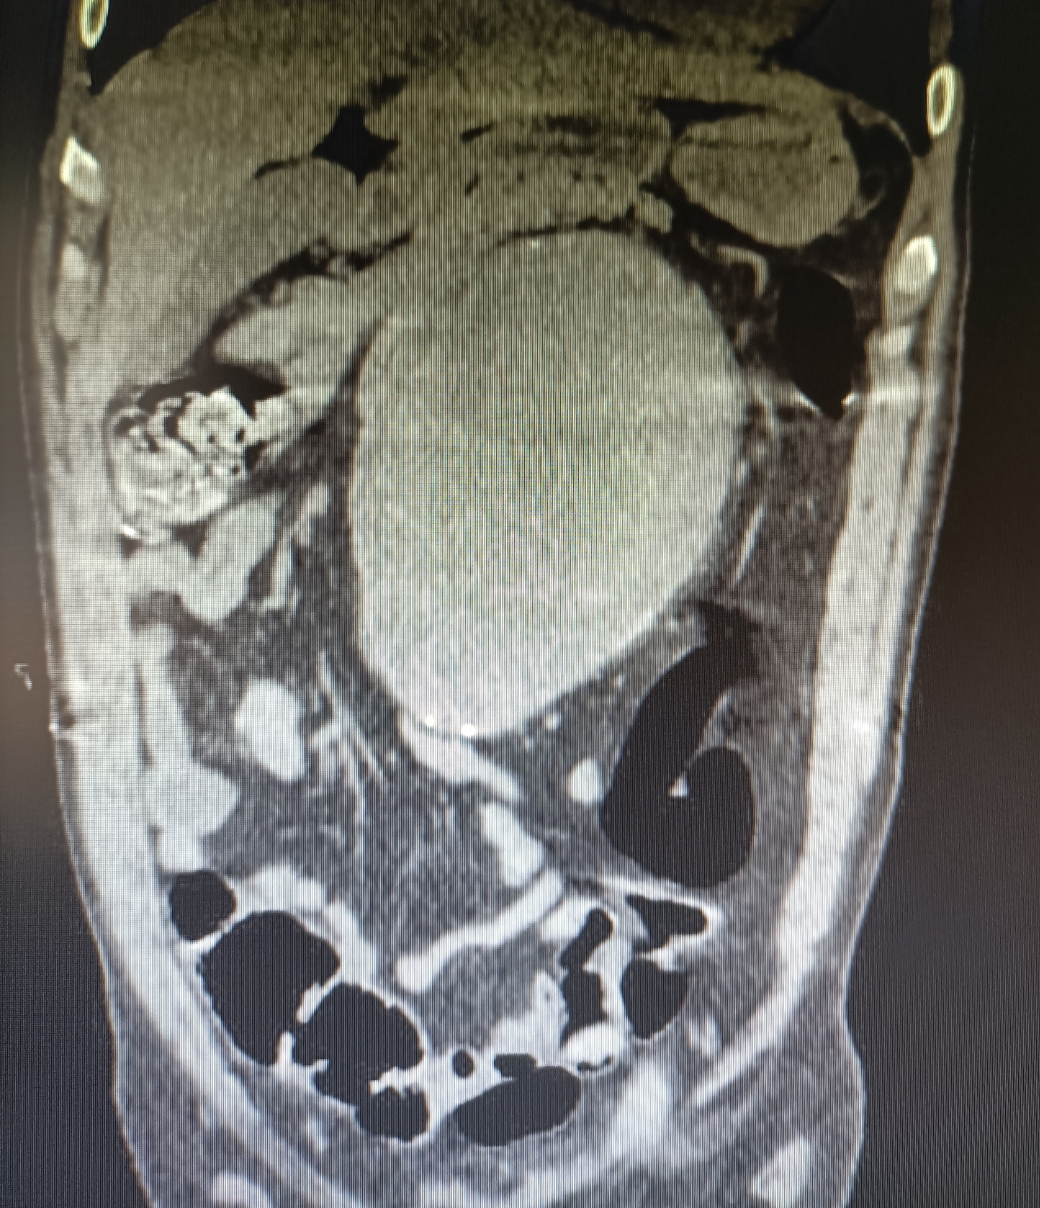

Se medica para control del dolor y se realiza Angio-TC de abdomen, donde se observan hallazgos compatibles con aneurisma de aorta abdominal infrarrenal de unos 14 x 13 cm que se extiende hasta bifurcación ilíacas, con calcificación intimal y trombo semilunar, con signos de rotura inminente.